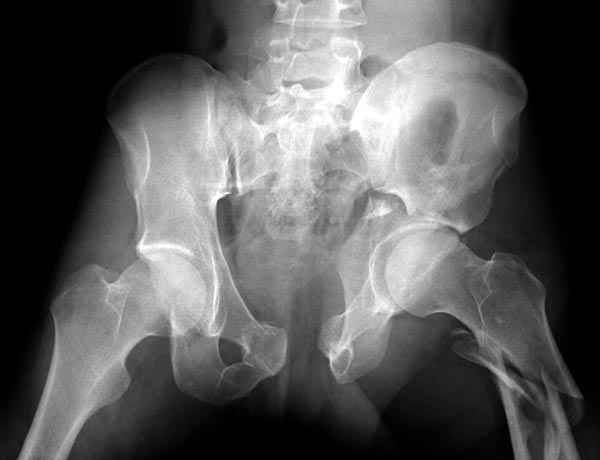

Интересно было бы посмотреть рентгенограммы до операции. У меня впечатление, что я не все вижу, что тут есть... Уважаемые Господа "тазисты" и "тазологи", к какому типу переломов вертлужной впадины по Летурнелю вы бы отнесли это случай?

Из переломов проходящих через крыло и/или заднюю стенку ни простой перелом "передней колонны" (явно имеется пером задней стенки, и не видно перелома седалищной или лонной), ни простой "поперечный", ни ассоциированный "Т-образный" (т.к есть перелом крыла и не видно перелома седалишной), ни ассоциированный "задняя колонна+задняя стенка", на ассоциированный "поперечный+задняя стенка", ни ассоциированный "передняя колонна+задняя гемисфера" (не видно перелома седалищной), ни ассоциированный "обе колонны" (не видно перелома лонной седалищной) не подходят под эту классификацию....

к таковым себя не причисляю, но...обычное дело для нашей страны - выкладывать 3D и не показывать стандартные проекции Judet. Дигност представляет те ракурсы, которые по-его мнению наиболее информативны, более того комп сам достраивает какие-то мелкие повреждения по 3D по своему усмотрению. По данной реконструкции можно предполагать высокий двухколонный перелом с оскольчатыми передней и задней колоннами, оскольчатую высокую переднюю колонну с задним полупоперечником или одно из перечисленных с вовлечение КПС. У меня впечатление за второй вариант, но нужно обследовать нормально - проекции, сканы.

Судя по представленным реконструкциям (не очень хорошего качества - много наводок)

мы имеем дело с полупоперечным переломом у которого отломался задний край или его отломали, превратив перелом в полный двухколонный.

По отдельным срезам и тем более по реконструкции трудно судить о сращении крыла и задней колонны с осевым скелетом.

В большинстве случаев при двухколонных переломах

в итоге получается прочный бублик с дыркой. При эндопротезировании в дырку помещается головка, а чашка должна неплохо заклиниться в бублике.

Главное, чтобы бублик не был разорван, что не очень понятно на представленных снимках.

Все выступающие коллеги высказались насчет необходимости стандартных снимков по Judet, потому что для определения тактики лечения переломов вертлужной впадины 3Д снимки малоинформативны.

Летурнель разработал классификсацию на основании прямого, запирательного и подвздошного рентген снимков, котоые, кроме описания характера переломов, также подсказывают адекватный доступ для репозиции перелома.

Из того минимума, что представлено, мне кажется, мы имеем дело с двухколонным переломом вертлужной впадины. Обычно медиальный (центральный) "вывих" головки встречаются в сложных двухколонных переломах со смещением.